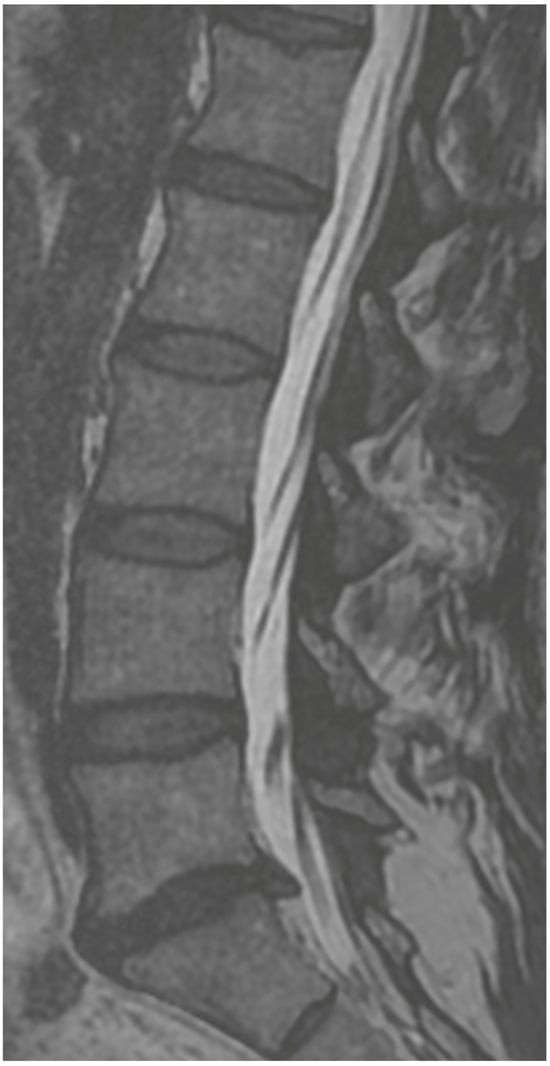

3.6. Case 3: Transient Paraparesis following Iatrogenic Vascular Fistula of the Dural Sac